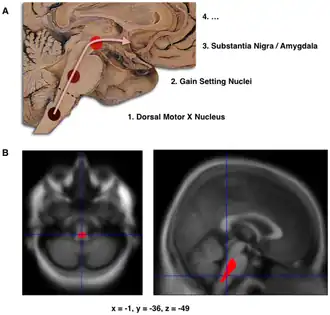

B. Lokalisering van het gebied waar een significante afname in hersenvolume zichtbaar is in beginnende Parkinson, vergeleken met een groep deelnemers die géén Parkinson hadden. Schade aan de hersenstam bleek bij deze studie mogelijk het eerste waarneembare stadium van neuropathologie bij de ziekte van Parkinson.[1]

De stadiëring van de ziekte van Parkinson werd voor het eerst beschreven door Heiko Braak in 2003.[4] Braak en zijn collega's stellen dat Parkinson begint wanneer een aanvaller van buitenaf het lichaam binnendringt via de neus of het gastro-intestinale systeem en het centrale zenuwstelsel (CZS) bereikt. De aanwezigheid van lewy-lichaampjes in het enterische en perifere zenuwstelsel onderbouwen deze stelling. De lewy-pathologie verspreidt zich door het CZS en raakt vooral dikke en grotendeels ongemyeliniseerde neuronen. Volgens Braak en collega's begint de ziekte in het enterische zenuwstelsel en treedt het het CZS binnen via de nervus vagus.[5]

Op basis van deze bevinding, hebben Braak en zijn collega's een stadiëringssysteem ontwikkeld, dat bestaat uit zes stadia. Elk stadium wordt gekenmerkt door abnormale pathologie in een specifieke neurologische structuur. Qua symptomatologie, nemen het type en de ernst van de kenmerken van de ziekte toe met elk hoger stadium.[6]